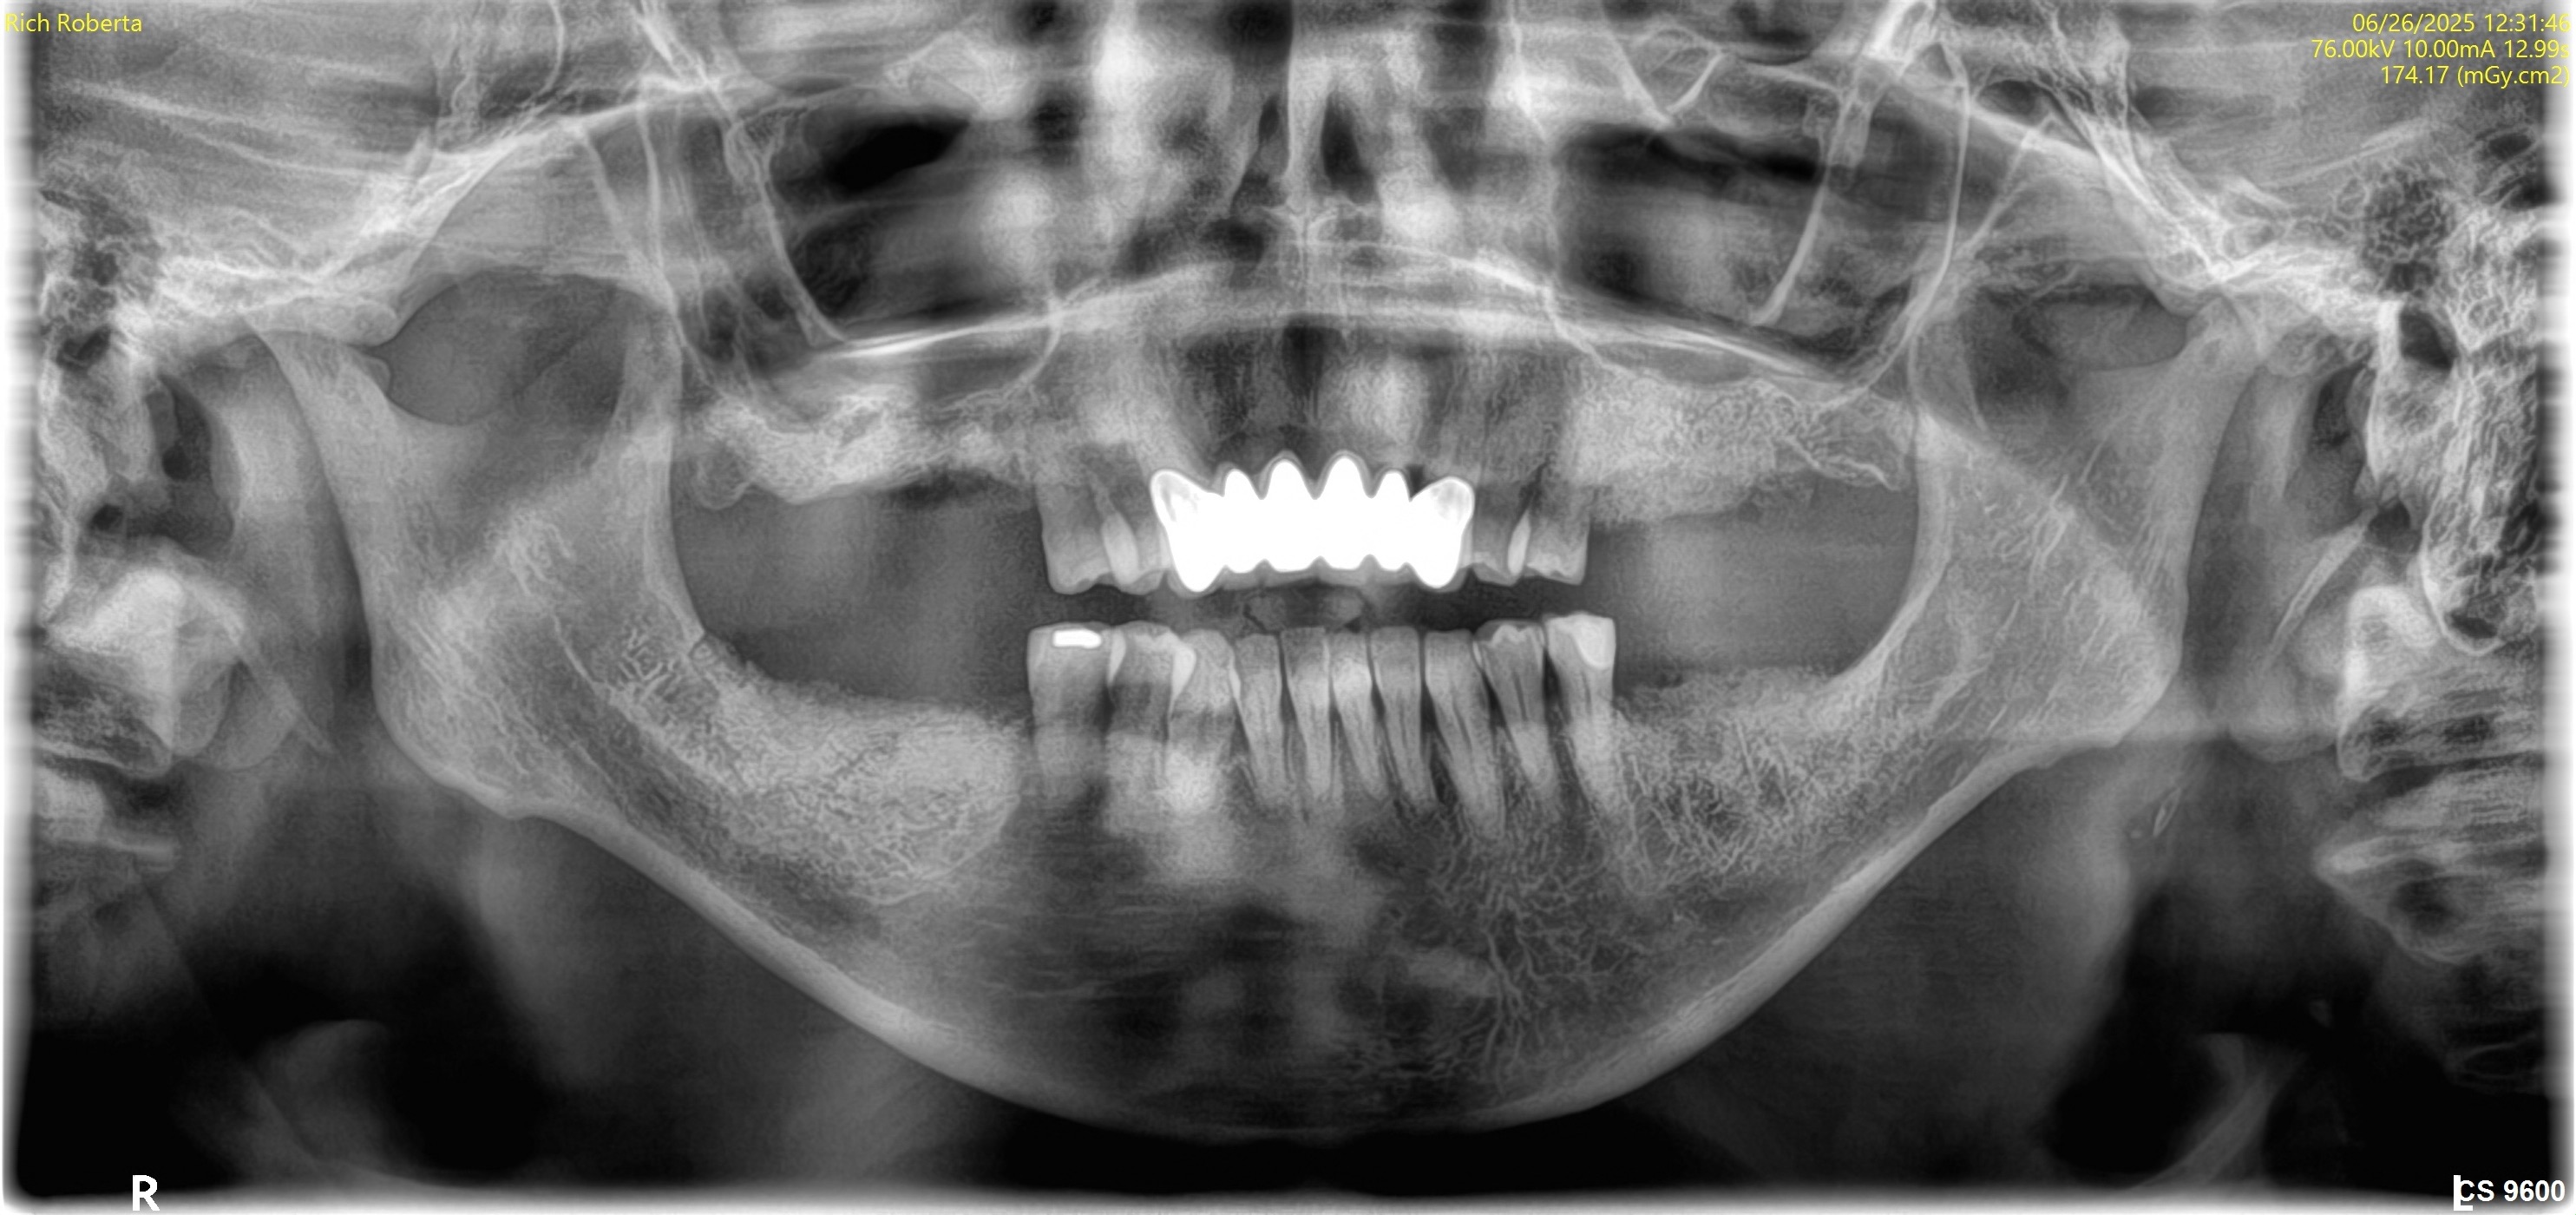

June 26, 2025Extractions with bone grafting (#14, #15, #18, #19).

Visual Case Progression

All clinical images are shown at a consistent size for easy comparison.

Before & After (Pano Images)